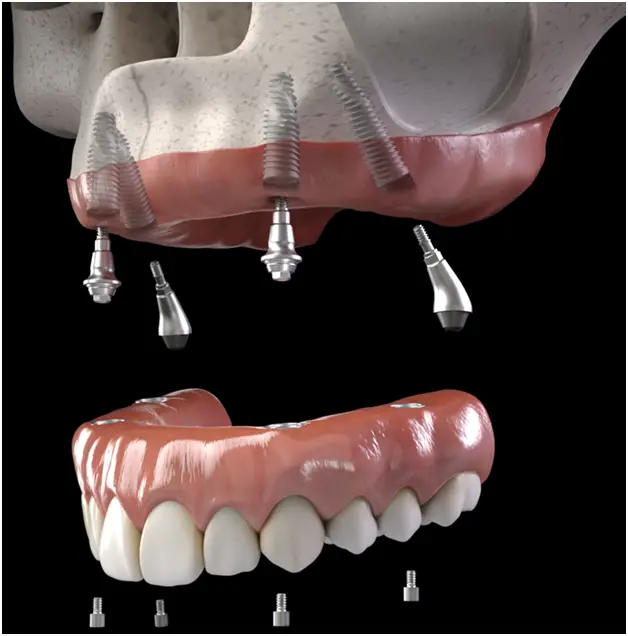

All-on-X is a modern dental implant procedure often used as a full-mouth restoration solution for people missing most or all of their teeth. The “X” in the name represents the number of implants used to support a full arch of replacement teeth, typically between 4 and 6 implants. This method provides a secure, stable, and long-lasting alternative to traditional dentures.

Once the implants are fully integrated, the permanent prosthesis is attached.